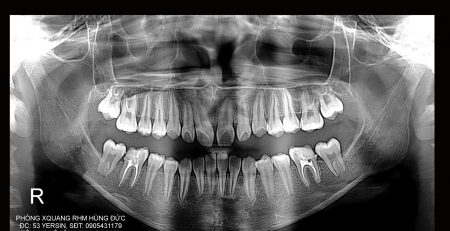

3. Phim toàn cảnh (panoramic): Khảo sát toàn bộ răng và xương hàm cả hàm trên và hàm dưới